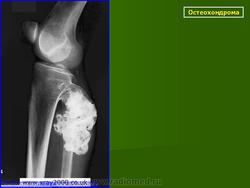

Локализация остеохондромы: частота поражения отдельных костей различна; нижний коней бедренной кости, верхние отделы плечевой и большеберцовой костей поражаются более чем у половины больных. На всем протяжении остеохондрома покрыта надкостницей. Она может быть обнаружена и в других костях, за исключением костей лицевого черепа. Все же поражение костей позвоночника, кистей рук и стоп встречается редко. При рентгенологическом исследовании видна типичная картина узкого или широкого выроста вблизи эпифизарной части пораженной кости. Обычно плотность узла неоднородная, имеются многочисленные плотные участки, соответствующие обызвествленным хрящевым долькам. Хрящевая «шапочка» большей частью не определяется, поскольку хрящ остается необызвествленным. Она может быть выявлена только при магнитно-резонансной томографии.

Остеохондрома.